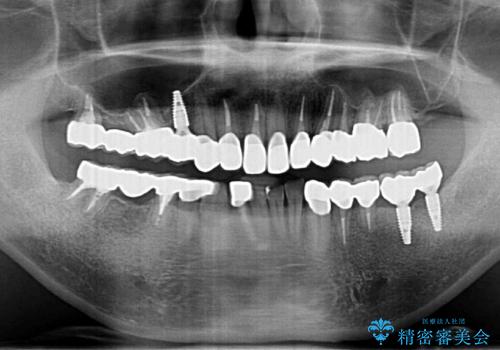

- 「少しずつ色々な箇所が悪くなり、歯医者に通い続けている。全ての歯を長持ちするような状態にできるような治療を受けたい。」、と全顎・総合的な治療を希望され来院されました。

根管治療・矯正治療・歯周外科・セラミック補綴を含む様々な治療オプションを駆使し、長期間良好な状態に保てるような治療計画を立案します。

矯正治療を絡めた総合的な治療をお行なったことで、理想的な咬合関係を確立し安定した噛み合わせで仕上げることができました。

また歯周外科を行うことで歯ぐきの腫れを改善し、清掃性を高めています。